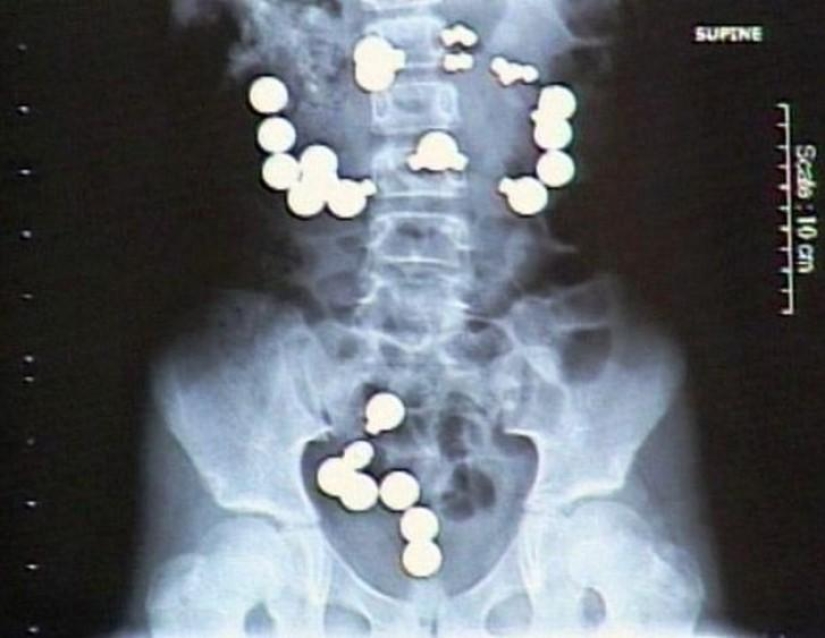

5. Magnets.

23. Methamphetamines.